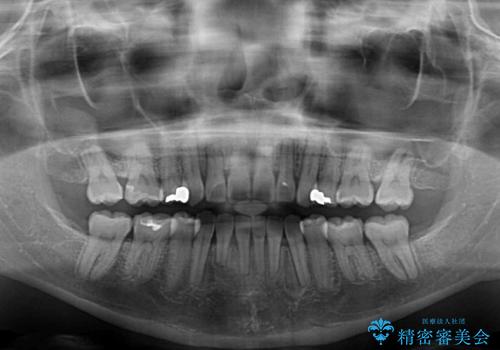

- 海外で抜歯矯正を開始し、治療途中で帰国したため、転院先を探しているとのことで来院された患者様です。

ワイヤーは抜けてしまい、後戻りが始まっている状態でしたが、既存の装置を継続利用して受け入れてくれる医院が見つからないとのことでした。

当院では、張り替える必要のある部位は張り替えることで継続することとし、抜歯スペースを閉じていくように治療を行うこととしました。

後戻りにリカバリーに少し時間を要しましたが、1年強の期間で無事に治療を終えることができました。